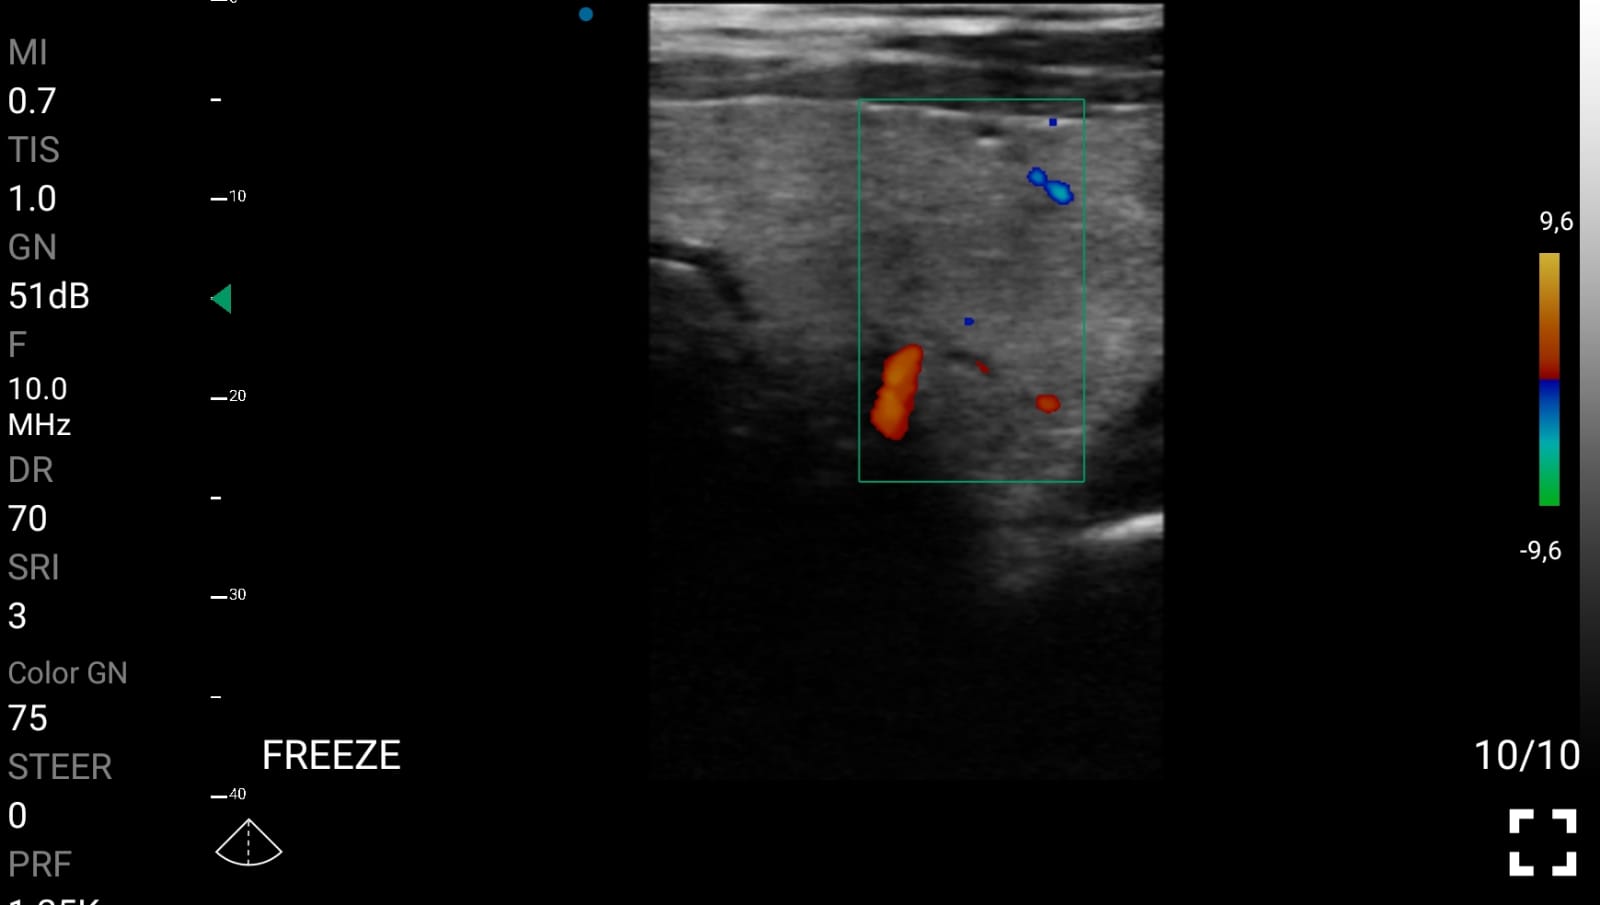

Η χρήση των ασύρματων κεφαλων MedBridge Echo Wave, ειδικά σχεδιασμένης για ενδοκρινολογικές ιατρικές πράξεις, ενισχύουν περαιτέρω την κλινική ακρίβεια και την αποτελεσματικότητα της διαχείρισης των ασθενών. Οι κεφαλές MedBridge Echo Wave επιτρέπουν την καθοδήγηση διαγνωστικών και θεραπευτικών παρεμβάσεων, όπως παρακεντήσεις και βιοψίες, τον ακριβή εντοπισμό και τη μορφολογική αξιολόγηση νεοπλασματικών αλλοιώσεων, καθώς και την παρακολούθηση της ανταπόκρισης στη θεραπεία. Παράλληλα, διευκολύνει τη διενέργεια ελάχιστα επεμβατικών πράξεων, προσφέροντας υψηλά επίπεδα ασφάλειας και ακρίβειας.

Ολες οι παραπάνω απεικονιστικές εξετάσεις έχουν ληφθεί από φορητή συσκευή όπως: Apple Iphone, Tablet, Samsung Mobile Phones και διάφορες άλλες φορητές συσκευές.